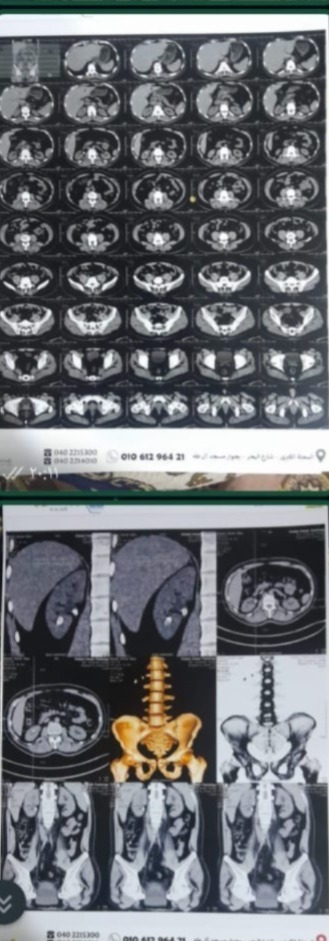

تحولت عملية بسيطة لشاب ثلاثيني لم يشتك من أمراض مزمنة إلى مأساة أودت بحياته بعد خضوعه لعملية تفتيت حصوات على الكلى بالمنظار بأحد المستشفيات الخاصة بالمحلة الكبرى، بعد ثلاث عمليات في يوم واحد، دون موافقة الأهل.

وقالت السيدة هاجر زوجة الشاب المتوفى الذي يدعى شريف أشرف عطية لـ "تليجراف مصر"، إن زوجها يبلغ 33 عامًا وكان لا يعاني من أي أمراض مزمنة قبل خضوعه لعملية تفتيت حصوات على الكلى بمستشفى بالمحلة الكبرى، والذي علم بمرضه بالصدفة دون شعوره بالتعب سابقًا .

وقالت هاجر إن الطبيب زعم أن زوجها كان يعاني من مرض بالقلب، ولم يخبره قبل إجراء العملية، وهو على عكس ما ظهر بالتحاليل والأشعة، كما يزال الطبيب يمارس عمله بشكل طبيعي إلى الآن، وطالبت الزوجة بحق زوجها الذي فقدته في شبابه، بعد تركه لطفلين لم يتخط عمر الكبير منهم الـ 7 سنوات في عملية بسيطة كانت تظن رجوعه معها بعد خضوعه لها إلى بيتهم حول أولاده.